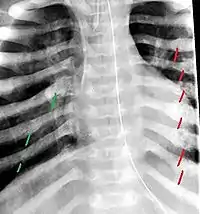

The material factual allegations of the amended complaint are as follows. Plaintiff was born on May 14, 1970. On repeated occasions during the first year of her life she was severely beaten by her mother and the latter's common law husband, one Reyes. On April 26, 1971, when the plaintiff was eleven months old, her mother took her to the San Jose Hospital for examination, diagnosis, and treatment. The attending physician was defendant Dr. Flood, acting on his own behalf and as agent of the defendant San Jose Hospital. At the time, the plaintiff was suffering from a comminuted spiral fracture of the right tibia and fibula, which gave the appearance of having been caused by a twisting force. Plaintiff's mother had no explanation for this injury. Plaintiff had bruises over her entire body. In addition, she had a non-depressed linear skull fracture which was then in the process of healing. Plaintiff demonstrated fear and apprehension when approached. Inasmuch as all plaintiff's injuries gave the appearance of having been intentionally inflicted by other persons, she exhibited the medical condition known as the battered child syndrome.

It is alleged that proper diagnosis of plaintiff's condition would have included taking X-rays of her entire skeletal structure, and that such procedure would have revealed the fracture of her skull. Defendants negligently failed to take such X-rays, and thereby negligently failed to diagnose her true condition. It is further alleged that proper medical treatment of plaintiff's battered child syndrome would have included reporting her injuries to local law enforcement authorities or juvenile probation department. Such a report would have resulted in an investigation by the concerned agencies, followed by a placement of plaintiff in protective custody until her safety was assured. Defendants negligently failed to make such report.

On this appeal plaintiff has expressly abandoned her claim of punitive damages. It is alleged that proper diagnosis of plaintiff's condition would have included taking X-rays of her entire skeletal structure, and that such procedure would have revealed the fracture of her skull. Defendants negligently failed to take such X-rays, and thereby negligently failed to diagnose her true condition. It is further alleged that proper medical treatment of plaintiff's battered child syndrome would have included reporting her injuries to local law enforcement authorities or juvenile probation department. Such a report would have resulted in an investigation by the concerned agencies, followed by a placement of plaintiff in protective custody until her safety was assured. Defendants negligently failed to make such report. The complaint avers that as a proximate result of the foregoing negligence plaintiff was released from the San Jose Hospital without proper diagnosis and treatment of her battered child syndrome, and was returned to the custody of her mother and Reyes who resumed physically abusing her until she sustained traumatic blows to her right eye and back, puncture wounds over her left lower leg and across her back, severe bites on her face, and second and third degree burns on her left hand.

For example, the leading article by Kempe et al., op. cit., supra,[10] states that "A physician needs to have a high initial level of suspicion of the diagnosis of the battered-child syndrome in instances of subdural hematoma, multiple unexplained fractures at different stages of healing, failure to thrive, when soft tissue swelling or skin bruising are present, or in any other situation where the degree and type of injury is at variance with the history given regarding its occurrence . . . ." (Id., at p. 20.) Of the different types of fractures exhibited, an arm or leg fracture caused by a twisting force is particularly significant because "The extremities are the 'handles' for rough handling" of the child by adults. (Id., at p. 22.) The article also contains numerous recommendations to conduct a "radiologic examination of the entire skeleton" for the purpose of confirming the diagnosis, explaining that "To the informed physician, the bones tell a story the child is too young or too frightened to tell." (Id., at p. 18.) Finally, on the subject of management of the case it is repeatedly emphasized that the physician "should report possible willful trauma to the police department or any special children's protective service that operates in his community" (id., at p. 23) in order to forestall further injury to the child: "All too often, despite the apparent cooperativeness of the parents and their apparent desire to have the child with them, the child returns to his home only to be assaulted again and suffer permanent brain damage or death." (Id., at p. 24.)